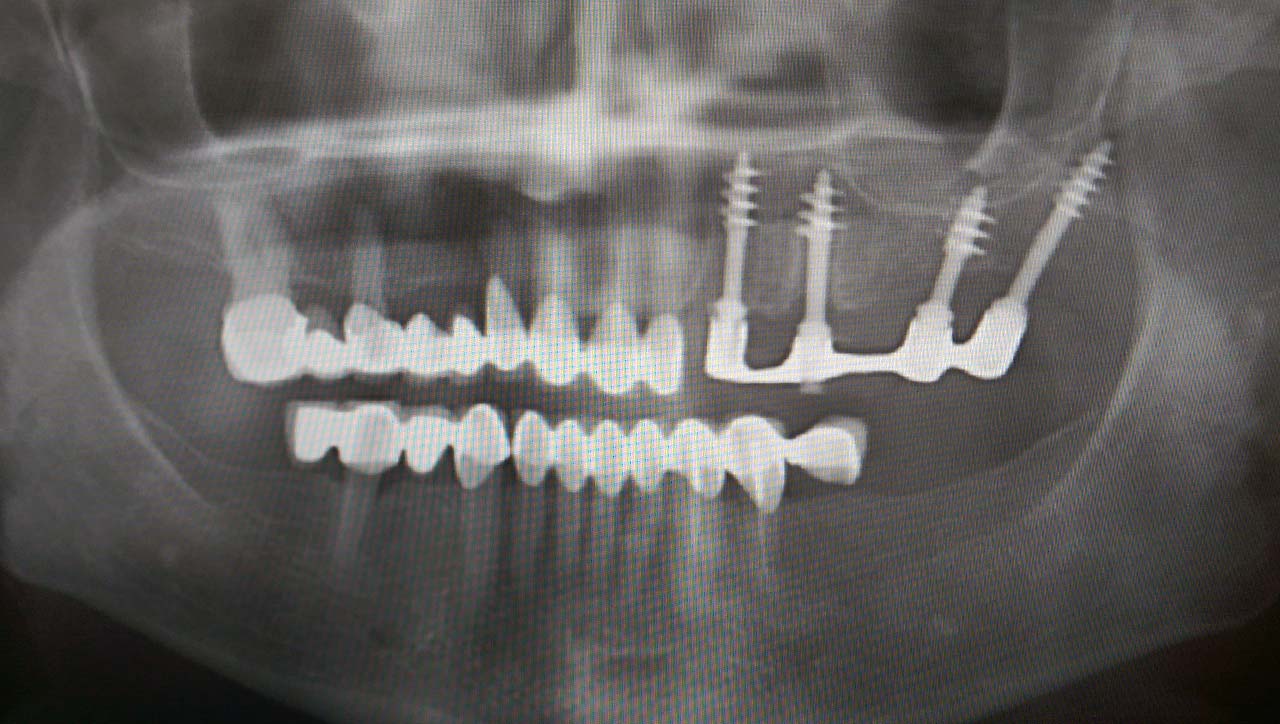

Teljes fogatlanság helyreállítása 2 nap alatt

Teljes fogatlanság helyreállítása 2 nap alatt azonnal terhelhető svájci IHDE implantátumokkal és PMMA műanyag hidakkal. Intraorális szkennerrel vettünk lenyomatot az implantáció után, és erre a digitális mintára készítette el a fogtechnika a hidak digitális tervezését, majd faragta ki műanyagból. Ezt a gyors munkát az azonnal terhelhető implantátumok és a digitális lenyomat, tervezés segítségével tudtuk megcsinálni mindössze 2 nap alatt. Dr. Kelemen Péter és a Symbion Fogtechnika munkája.